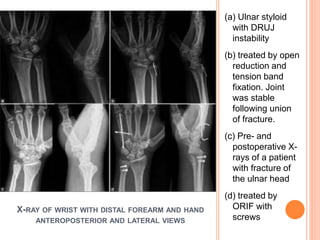

X-RAY OF WRIST WITH DISTAL FOREARM AND HAND

ANTEROPOSTERIOR AND LATERAL VIEWS

(a) Ulnar styloid

with DRUJ

instability

(b) treated by open

reduction and

tension band

fixation. Joint

was stable

following union

of fracture.

(c) Pre- and

postoperative X-

rays of a patient

with fracture of

the ulnar head

(d) treated by

ORIF with

screws